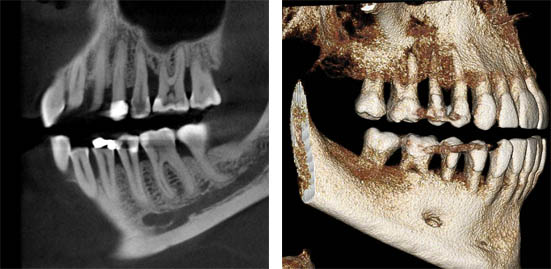

Case2: Maxillary impacted canine tooth

Slight shadow can be seen in the panoramic image. In the 3Dimage (MPR:Cpronal), the state of the eruption and the position of the maxillary impacted canine tooth can be accurately evaluated. Further detailed information can be obtained in the image of 3D VR.

2D (Panoramic image) 3D (MPR:Coronal) 3D VR